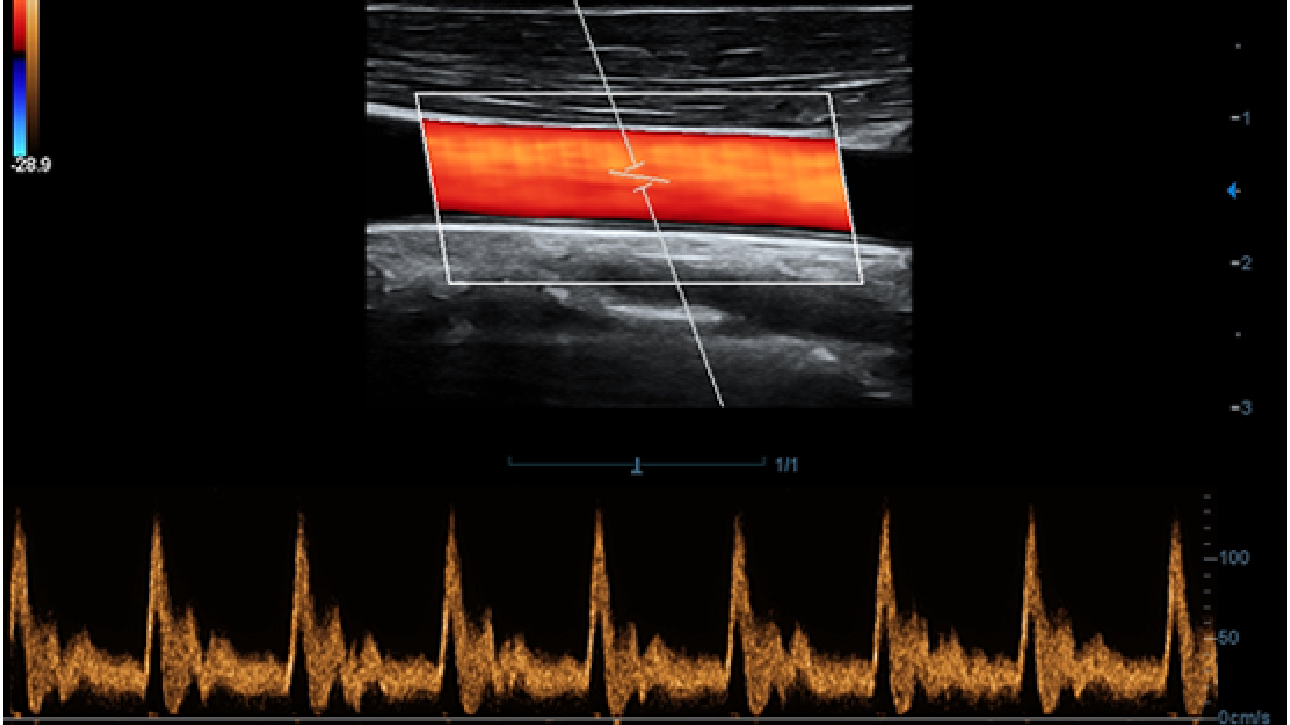

X-Insight ??? ??? ??? ??? ?? ??? ?? ?? ??????.

?????? ??? ???? ?? ???? ??? ??? ??? ???? ??? ??? ??? ?? ??? ???? ?????. ??? ?? ????? ???? ???? ??? ?? ??? ???? ?? ???? ??? ???? ???? ????.

???? ?? ??? ?????, X-Insight???? ??? DC-60 Exp ?? ??? ???? ???? ?? ??? ?? ??? ?? ???? ?????.

X-Insight??? ??? DC-60 Exp? ??? ??? ?? ?? ???? ???? ???(eXpress) ???, ???(eExceptional) ?????, ???? (eXceeding) ?? ??? ?? ????, ??? ???? ??? ??? ?? ???? ?????.